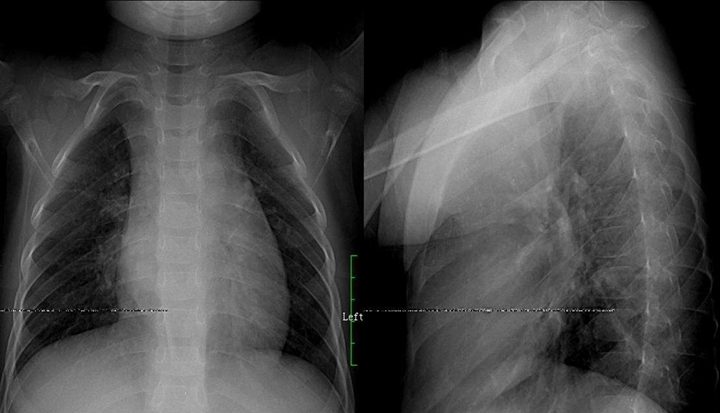

肺结核:肺结核分五类型,原发血播浸结其,原发肺内淋巴引,血播急粟三均匀,慢播新老病灶模糊,浸润渗出片絮球,慢纤空洞蜂窝柳,胸膜炎见结核多,确定三期疗效后估,临床影征痰检为依据,菌量毒性免疫力,鉴别诊断炎性先,肺癌转移假瘤辨。备注: 蜂窝柳---一形如蜂窝状肺纹理呈垂柳征。

原发支气管肺癌:肺癌起源支上皮,组织大体类型别,中央肺癌四征像,不张气肿肿块肺炎,周围小癌边模糊,增大浓密边清楚,癌肿坏死空洞偏,脐凹兔耳癌索现,弥漫肺癌肺泡间,粟粒结节重叠囊。